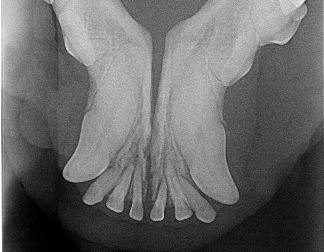

Zahn- und Zahnfleischprobleme sind häufige Erkrankungen unserer Haustiere.Sowohl Hunde als auch Katzen neigen zu Zahnstein, Zahnfleischentzündung und Zahnfleischschwund. Beim jährlichen Gesundheitscheck werden die Maulhöhle und die Zähne ihrer Lieblinge routinemäßig untersucht. Viele Besitzer klagen über Mundgeruch ihrer Vierbeiner, welcher eines der häufigsten Anzeichen von Zahnproblemen darstellt. Hinter einem üblen Mundgeruch kann sich manchmal sogar ein eitriger Zahn verstecken, der unbehandelt erhebliche Schmerzen verursachen kann. Mit der Hilfe modernster zahnmedizinischer Geräte kann hier Abhilfe geschaffen werden. Auch über diverse Präventionsmöglichkeiten berate ich Sie gerne. Im Sinne unserer Lieblinge gilt: Je früher das Problem erkannt wird, desto weniger Schäden werden hinterlassen. Aufgrund der kurzen Schnauze sind Mops, Bully und Co. häufiger von Zahnproblemen betroffen